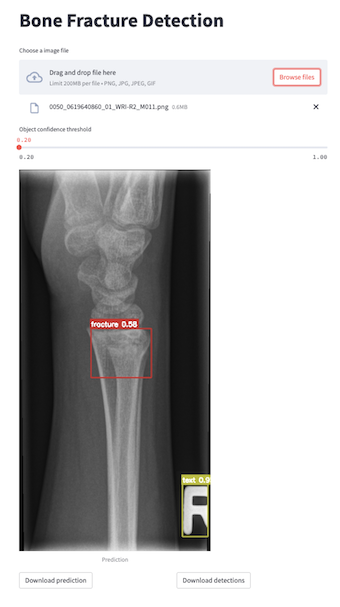

streamlit run app/webapp.py

Fig3: Bone Fracture Detection WebApp made with streamlit.

docker pull mdciri/bone-fracture-detection:latest

docker run -p 8501:8501 mdciri/bone-fracture-detection